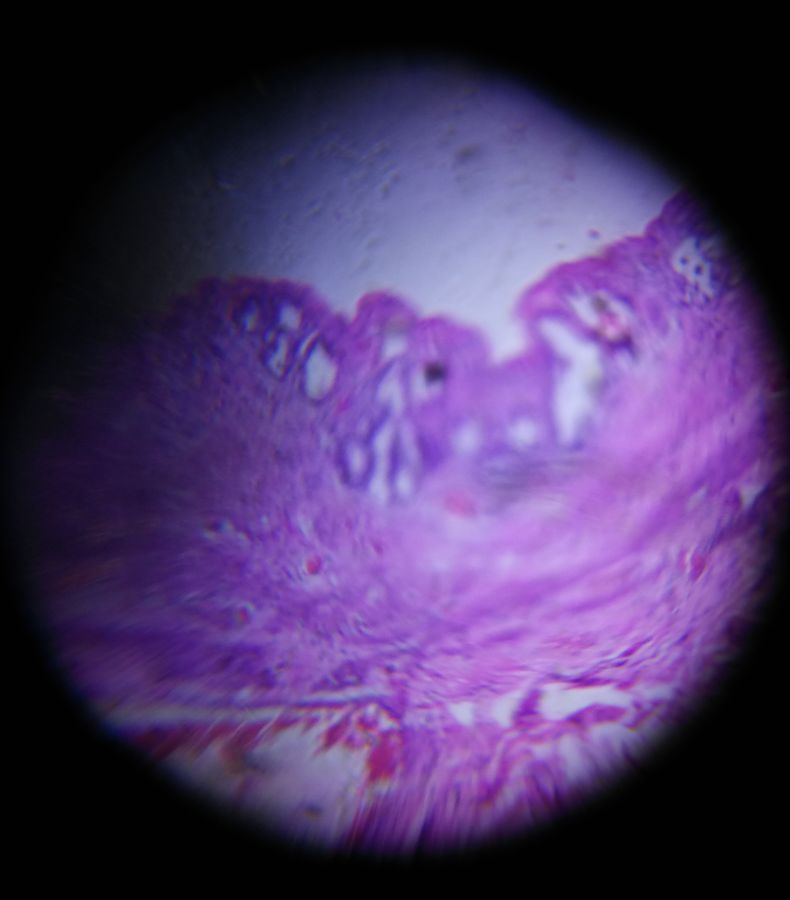

Cholelithiasis

Applause Icon140x Magnification

Section from Gall Bladder showing flattened mucosal lining fibrous thickening as seen under Foldscope from Department of Pathology of R D gardi Medical College, Ujjain